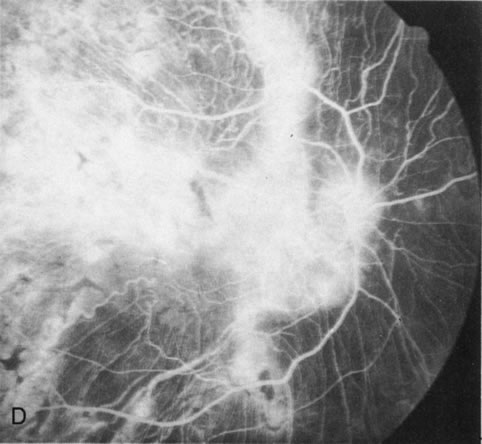

Fig. 4. Choroideremia and choroideremia carrier. A. The choroidal atrophy in this affected male is not apparent in the fundus. B. However, the angiogram shows diffuse atrophy of the choriocapillaris with persistent visualization of the larger choroidal vessels. C. This carrier female has peripapillary choroidal atrophy and diffuse pigment mottling. D. The patchy areas of focal choroidal atrophy that occasionally occurs in carriers is evident on angiography.

The typical carrier female, with focal or diffuse pigment mottling, does not show choroidal atrophy. However, a few carrier females have a more severe form with focal areas of choroidal atrophy. The presence of these areas, and possible progression, can be documented by FA (Fig. 4C and D). These carriers exhibit a mosaicism, which is explained by the Lyon hypothesis of random X-chromosome inactivation.